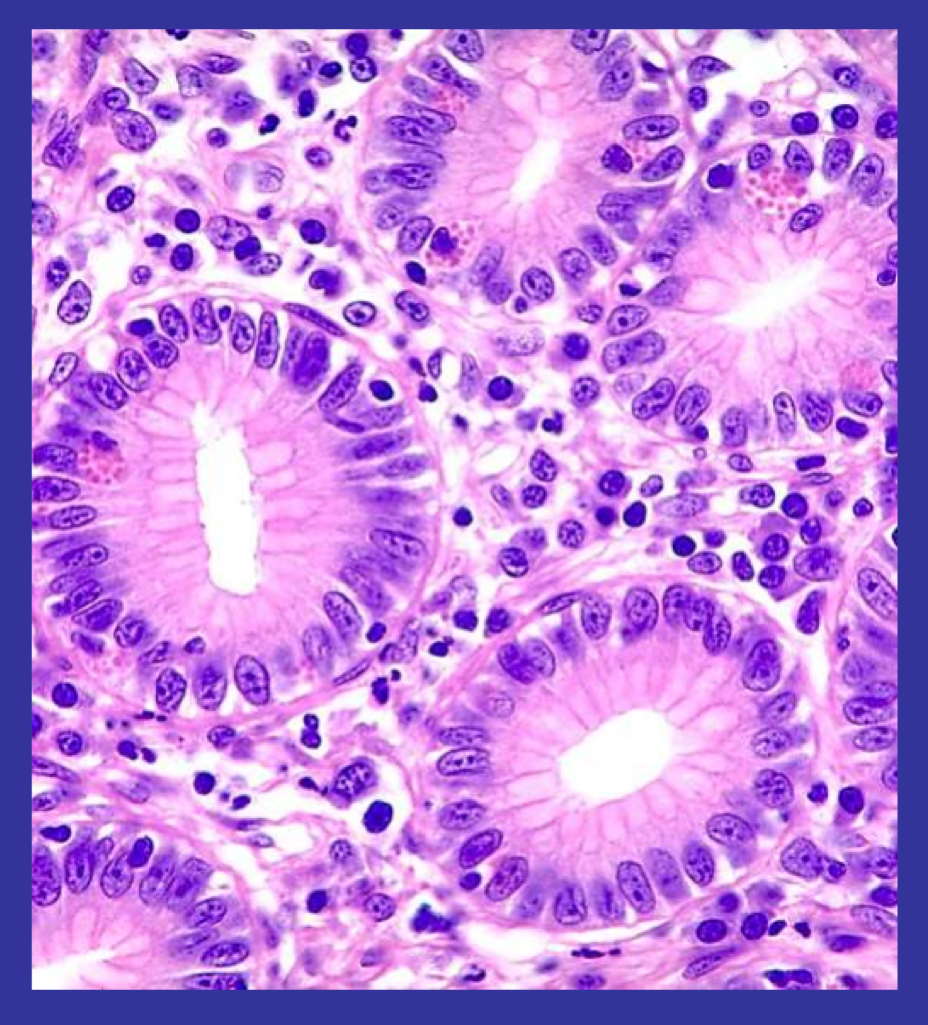

A - Brush border of microvilli

B - A pale-staining goblet cell which secretes mucus

C - Simple columnar epithelium - containing dark basally positioned nuclei

D - The epithelium rests upon a basement membrane

E - Subtending loose connective tissue, called lamina proproa, carries fine blood vessels and lymph vessels